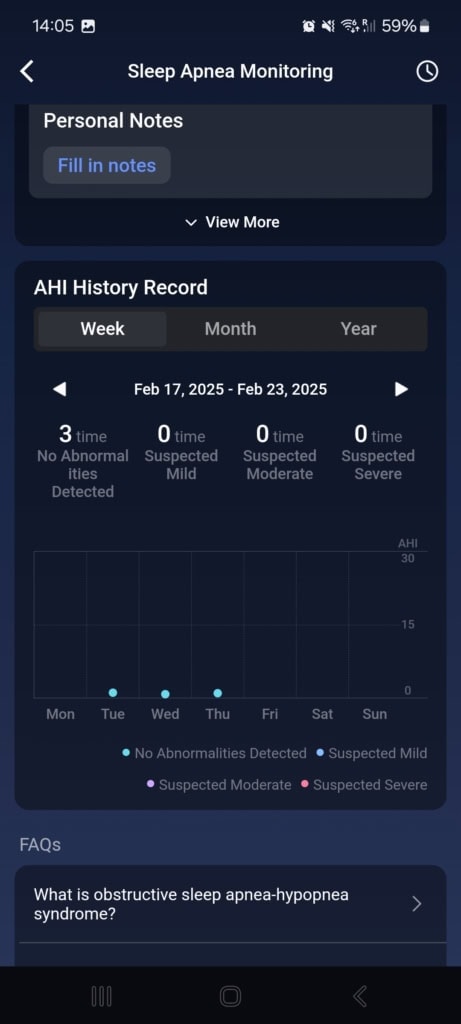

Monitorowanie bezdechu sennego

Na podstawie wahań saturacji krwi i tętna w nocy uzyskasz swój wskaźnik bezdechu-hipopnoe (AHI), który oznacza średnią liczbę epizodów z całkowitym zatrzymaniem oddechu i płytkim oddychaniem. Im wyższy wskaźnik, tym poważniejsze może być twoje zaburzenie.

Aby uzyskać kompleksową analizę, smart ring potrzebuje trzech nocy, podczas których wykrywa nieprawidłowości oddechowe. Na podstawie ustalonego wskaźnika dochodzi do zmiany trybu monitorowania. Użytkownicy z niskim lub zerowym wskaźnikiem nie wymagają dalszego monitorowania. Osoby w strefie lekkiego bezdechu mogą zmienić tryb na jedno automatyczne pomiarowanie w celu weryfikacji wyniku. W przypadku wysokiego wskaźnika i podejrzenia średniego do ciężkiego bezdechu dostępne jest codzienne automatyczne monitorowanie.

Po trzech nocach mój wskaźnik wyniósł 0, 0,2 i 0,3 i nie wykryto żadnych nieprawidłowości. Wartość jest bardzo odległa od dolnej granicy lekkiego bezdechu (5,5), więc nie było potrzeby dalszych pomiarów. Ponieważ nie cierpię na obturacyjny bezdech senny, nie pozostaje mi nic innego jak zgodzić się z tą oceną.